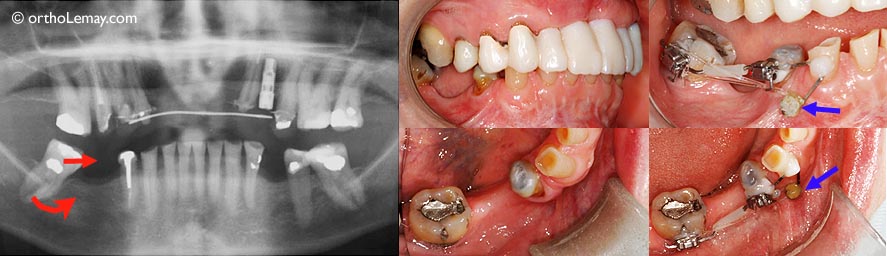

(A) Deuxième molaire supérieure qui est descendue (flèche) contre la molaire inférieure endommagée.

(B) 2 mini-vis ont été utilisées, une de chaque côté de la dent, pour servir d’ancrage à un ressort qui “remontera” la dent.

(C) Vue à l’aide d’un miroir qui montre les 2 vis, une du côté de la joue et l’autre du côté du palais (flèches).

(D) Un élastique peut aussi être utilisé pour exercer la force nécessaire à intruder la dent.